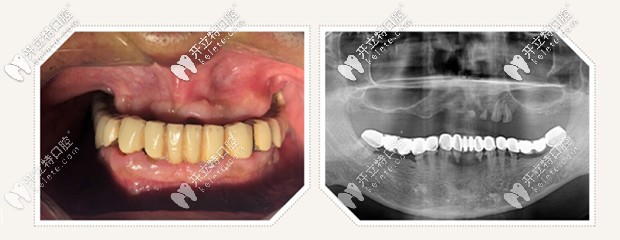

all on 4即刻種植,只需要植入4顆種植體,就把老爸上半口牙就全給修復(fù)啦,并且是當(dāng)天修復(fù),當(dāng)天戴牙啊,感覺太神奇啦!

All-on-4即刻種植牙效果圖

給老爸做的all on 4半口即刻種植牙花了10萬左右, 價格還是可以接受的,畢竟這做完種植牙的效果擺在這呢,上下半口牙齒恢復(fù)了咀嚼功能,近距離交談也看不出來做了種植牙,還有感覺老爸瞬間年輕了許多。